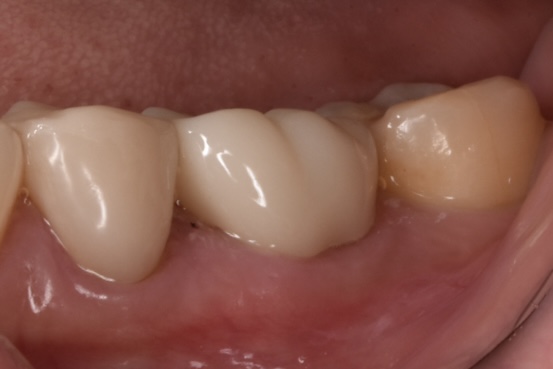

モニター様②

奥歯のやりかえです。真ん中に写っている左下奥歯(左側下顎第一大臼歯)の再治療です。神経治療からやり直しています。*色彩セラミックプラン